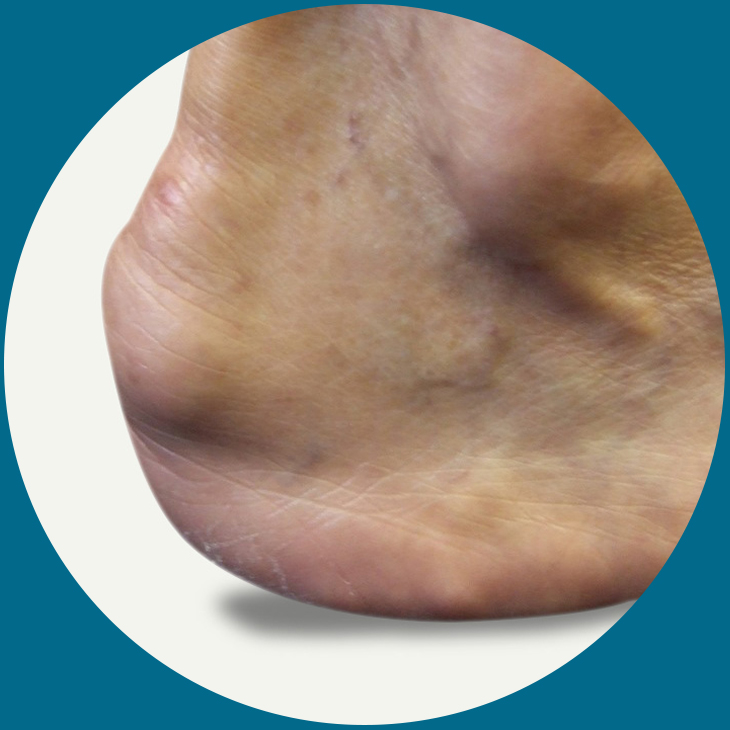

Haglunds heel bumps are formations of bony material that appear on the back of the heels. As the bony enlargement develops a small fluid filled sac can also develop which is called a bursa. When this sac becomes inflamed a condition called bursitis can occur which is very painful in most cases. It may also cause sensitivity and inflammation of the surrounding tissues such as those associated with the Achilles tendon. They can appear on either foot or both equally.

Initially the condition may be treated conservatively as this is less invasive and means the person is less likely to suffer side effects and complications of invasive methods. Pain relief, rest and ice application may help to reduce the discomfort, redness and swelling of the area which may be enough to ease the condition during flare-ups.

Those with hereditary problems such as high arches may find that orthotic devices such as heel pads or shoe inserts may help as this will relieve many of the problems associated with high arches. Soft shoes and those that do not contain hard or constricting backs may help as these will allow the foot and heel to assume their natural shape incorporating the additional bony structure that is a Haglunds bump.

For those who have not had any success with these methods or those whose bump protrudes quite significantly surgery may be recommended.

Haglunds heel bumps are formations of bony material that appear on the back of the heels. As the bony enlargement develops a small fluid filled sac can also develop which is called a bursa. When this sac becomes inflamed a condition called bursitis can occur which is very painful in most cases. It may also cause sensitivity and inflammation of the surrounding tissues such as those associated with the Achilles tendon. They can appear on either foot or both equally.

Initially the condition may be treated conservatively as this is less invasive and means the person is less likely to suffer side effects and complications of invasive methods. Pain relief, rest and ice application may help to reduce the discomfort, redness and swelling of the area which may be enough to ease the condition during flare-ups.

Those with hereditary problems such as high arches may find that orthotic devices such as heel pads or shoe inserts may help as this will relieve many of the problems associated with high arches. Soft shoes and those that do not contain hard or constricting backs may help as these will allow the foot and heel to assume their natural shape incorporating the additional bony structure that is a Haglunds bump.

For those who have not had any success with these methods or those whose bump protrudes quite significantly surgery may be recommended.